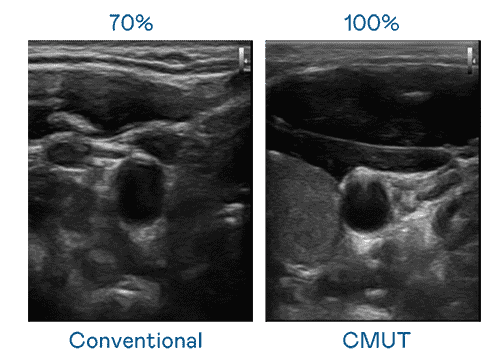

CMUT 技术是一种用电容式微机电元件来产生超音波讯号的技术。。与传统 PZT 压电式技术相比,,,CMUT 频宽增加 30%,,更宽频的超音波讯号让影像解析度大幅提升,,,,是实现高影像品质医疗超音波扫描、、促进精准医疗发展的关键技术。。

超音波影像的解析度高低,,,首先取决于探头能发出的讯号频宽。。彩运网 CMUT 可提供高清晰的超音波讯号,,提供高频宽、、、、高灵敏度、、、影像纹理细节更高的超音波影像,,,,协助医护人员缩短影像判读时间及利用精准的医疗影像进行诊断。。。